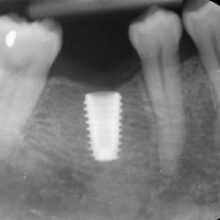

2. Treatment

Once you are numb, our dentist will surgically place the implant into the jawbone. The implant will need 3-6 months to heal, during which osseointegration will take place where there is a connection between the jawbone and the implant.